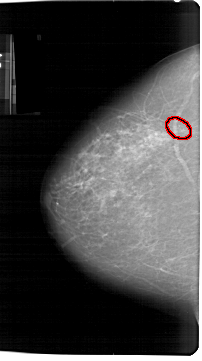

A_1300_1.RIGHT_CC

RIGHT_CC LINES 6346 PIXELS_PER_LINE 3496 BITS_PER_PIXEL 12 RESOLUTION 43.5 NON_OVERLAY